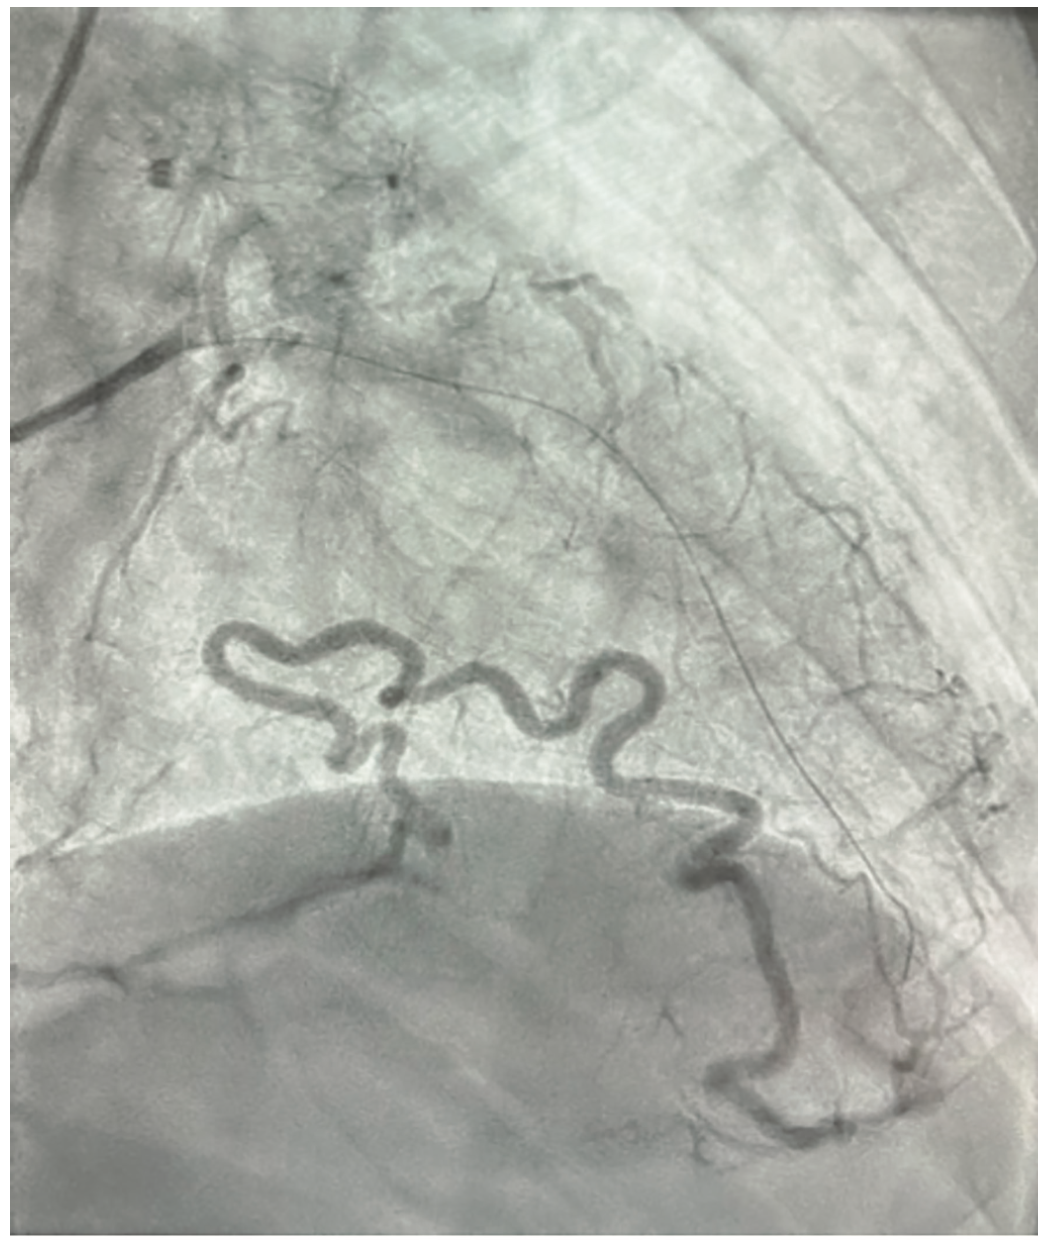

The patient is a 76-year-old male with a past medical history of hypertension, peripheral arterial disease (PAD), myocardial infarction (MI) two years ago, and hyperlipidemia, presenting with dyspnea on exertion. He was suspected of having coronary artery disease (CAD) after an abnormal stress test, and subsequently underwent a left and right coronary artery catheterization through the right radial artery. The patient was given 2 mg of midazolam and 200 mcg of fentanyl intravenously for a total sedation time of less than a minute. Access was achieved using a modified Seldinger technique with a 6 French catheter placed in the right radial artery. A 5 French catheter was then placed to engage the left coronary artery. Angiography showed a patent left main coronary artery and an 80% stenosis in the mid LAD. There was a small, patent, non-dominant LCX, and a dominant RCA with a chronic total occlusion and evidence of left and right collaterals. The ejection fraction was 60% and left ventricular end diastolic pressure was 14 mmHg. The LAD was noted to have an unusual course across the anterior heart. The extension of the LAD wrapped around the apex and supplied a large portion of the posterior heart, providing left and right collaterals. After further consideration, this vessel was identified as the left obtuse marginal artery coming off the LAD rather than the left circumflex artery, suggesting an anomalous coronary artery (Figures 1-3). Due to the patient’s multivessel CAD, cardiothoracic surgery was consulted for coronary artery bypass graft (CABG) evaluation. The patient underwent off-pump CABG x2 with left internal mammary artery to the LAD and a reverse saphenous vein bypass graft from the aorta to the distal RCA. He tolerated the procedure well and was subsequently taken to the cardiovascular intensive care unit in stable condition.